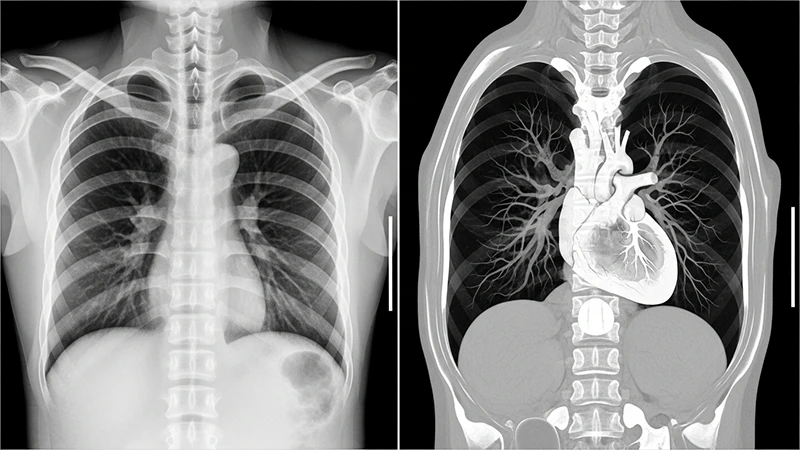

While a conventional X-ray provides a flat, two-dimensional view of the body, Computed Tomography (CT) represents a revolutionary leap forward. By combining X-ray technology with powerful computers, CT scanners produce detailed, cross-sectional images—or "slices"—of the body, allowing us to see inside with unprecedented clarity. It eliminates the overlapping of structures seen in standard radiography, providing a much clearer view of organs, bones, and soft tissues.

The computer's primary task is to perform a complex process called image reconstruction. It uses sophisticated algorithms to translate the thousands of projection measurements into a grid of pixels, where each pixel is assigned a specific shade of gray. This is not a random assignment; each shade corresponds to a calculated tissue density.